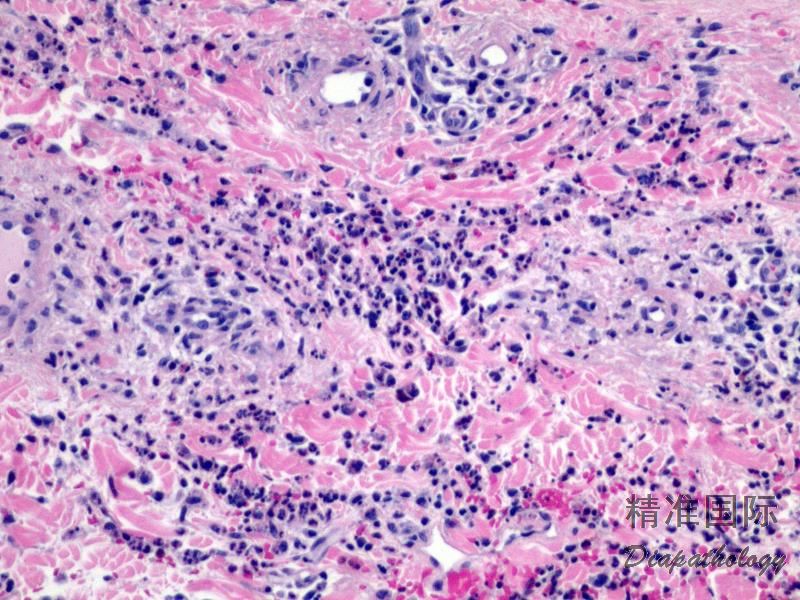

真皮过敏反应

Dermal Hypersensitivity Reaction